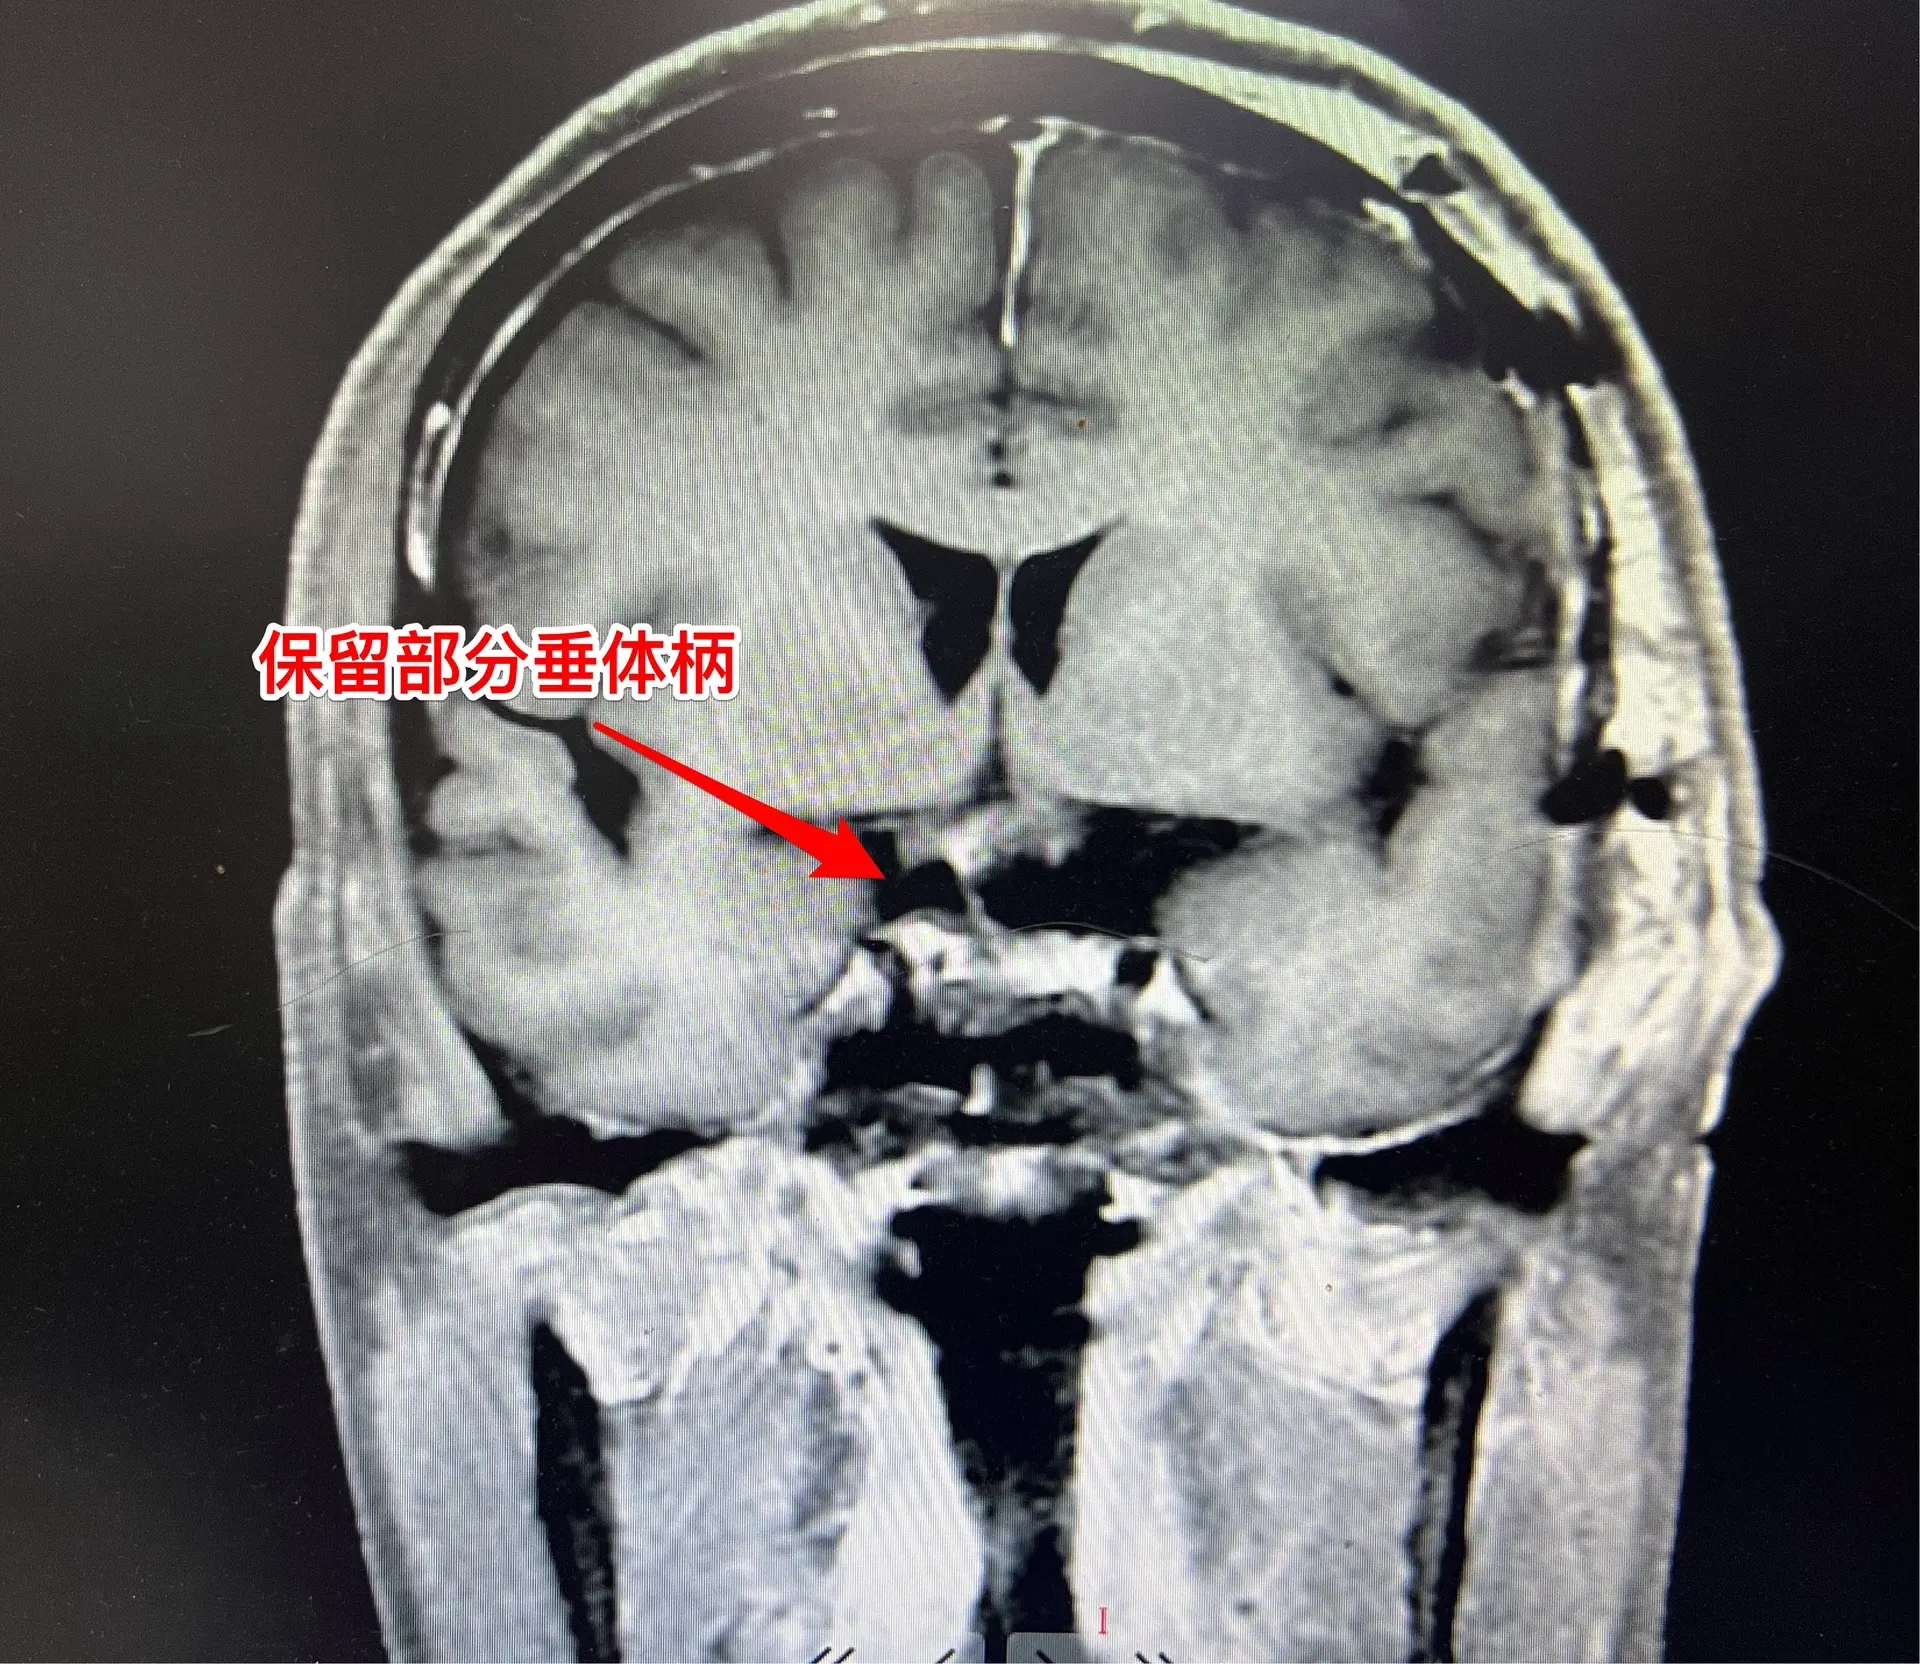

颅咽管瘤手术,出院3天就开车,合适吗?50岁的山东临沂男性,因头痛一年,左眼视力下降三个月于2024.8.16在我科住院。左眼视力0.1,右眼视力1.0。8月22日行开颅手术切除颅咽管瘤,手术后视力改善,身体恢复顺利,9月2日出院了,出院前测左眼视力0.5,右眼1.0。出院时精神好,体力好。 9月8日患者女儿和我联系,说患者出院三天就开车了。我告诉她,需要复查视力和视野,如果视野有缺损,开车是有风险的,不适合开车。